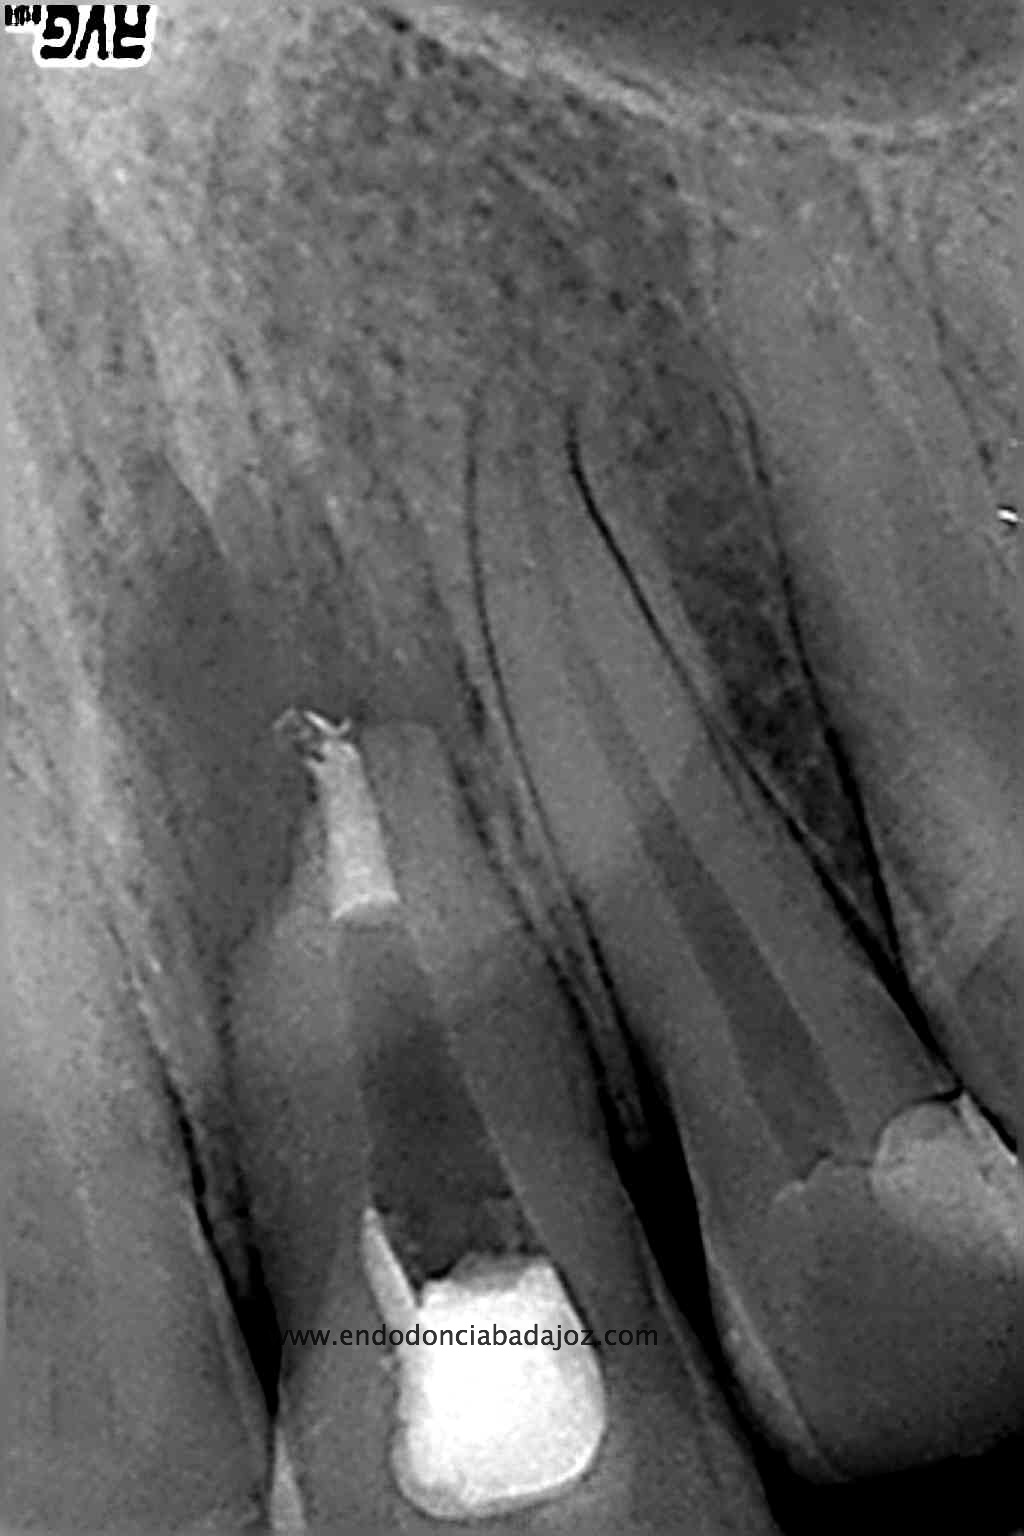

Intentamos eliminar toda la pasta de las paredes, determinamos el diámetro apical superior a 80, con lo que decidimos actuar colocando una barrera de M.T.A. (Trióxido Mineral Agregado) y hacer un backfilling con gutapercha inyectada.

Lo realizamos en dos sesiones, algo discutido entre compañeros, pero que en este caso, no dudo en absoluto,  pues presentaba una reabsorción apical. Incluso, a la hora de colocar el H de Ca, la medicación intraconducto elegida, decidimos extruirla.

Una vez que hemos transportado y barrera apical, hacemos el backfilling con la Pistola Obtura II.

(Rx Mesioradial)                                                               (Rx Ortoradial)